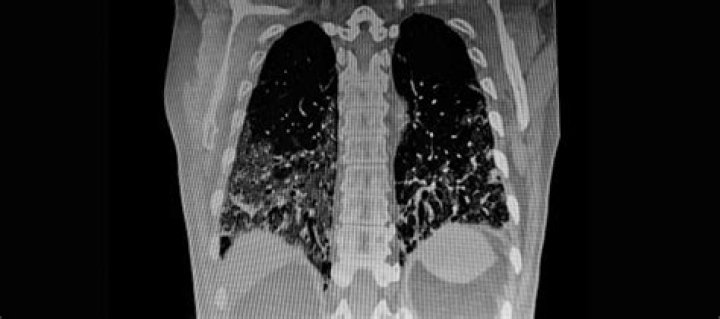

Does a lung CT scan show COPD?

A chest X-ray can show emphysema, one of the main causes of COPD . An X-ray can also rule out other lung problems or heart failure. CT scan. A CT scan of your lungs can help detect emphysema and help determine if you might benefit from surgery for COPD .

CT images can identify emphysema better and at an earlier stage than a chest x-ray. They can also identify other changes of COPD such as enlarged arteries in the lungs. CT is sometimes used to measure the extent of emphysema within the lungs.

CT technology is used to detect pulmonary nodules, collections of abnormal tissue in the lungs that may be early manifestations of lung cancer. These nodules are often detectable by CT before physical symptoms of lung cancer develop.

Although the CT scan cannot give a definitive diagnosis, it is helpful in the evaluation of lung diseases and conditions such as pneumonia, cancer, blood clots or damage caused by smoking.